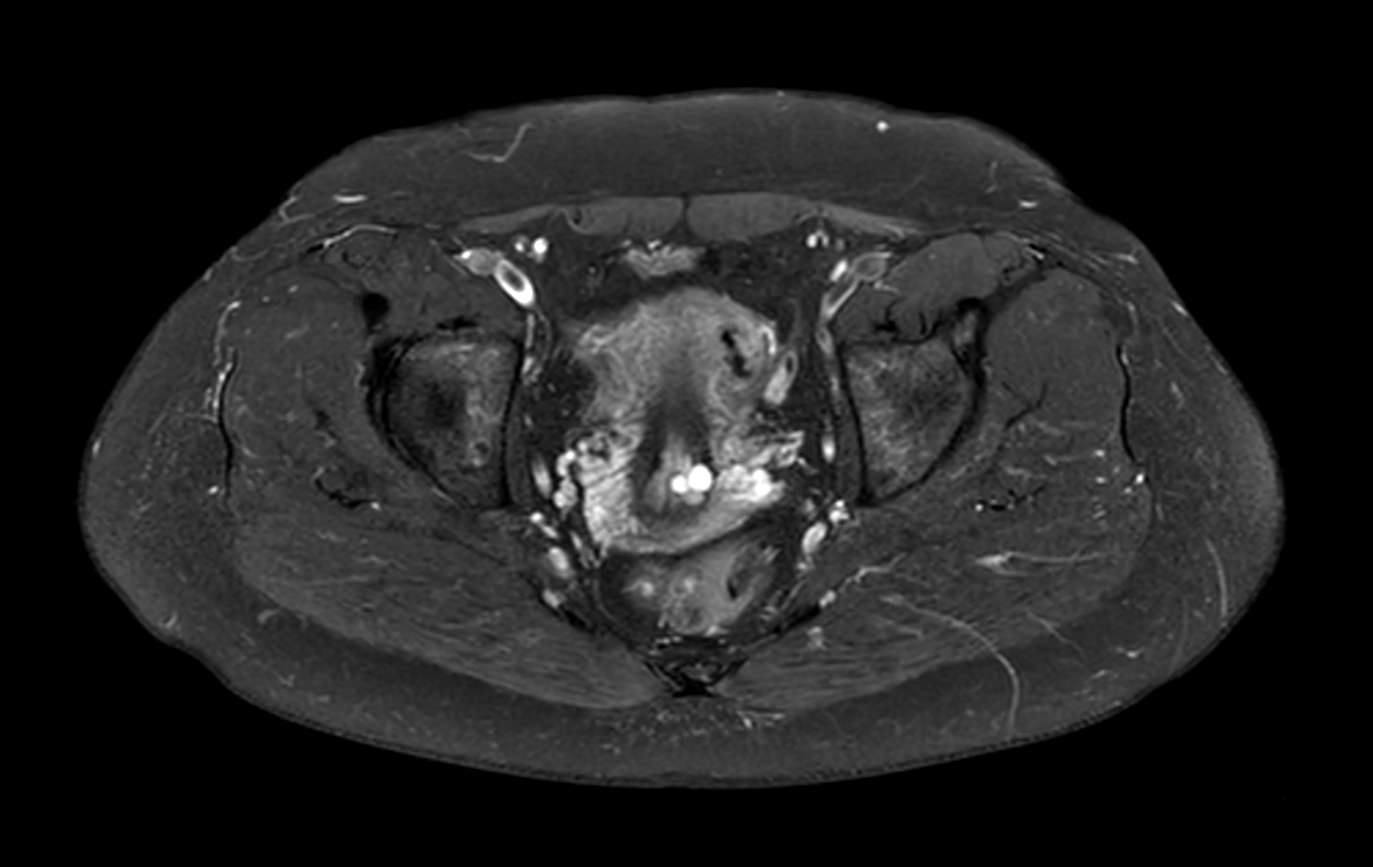

Axial STIR TSE